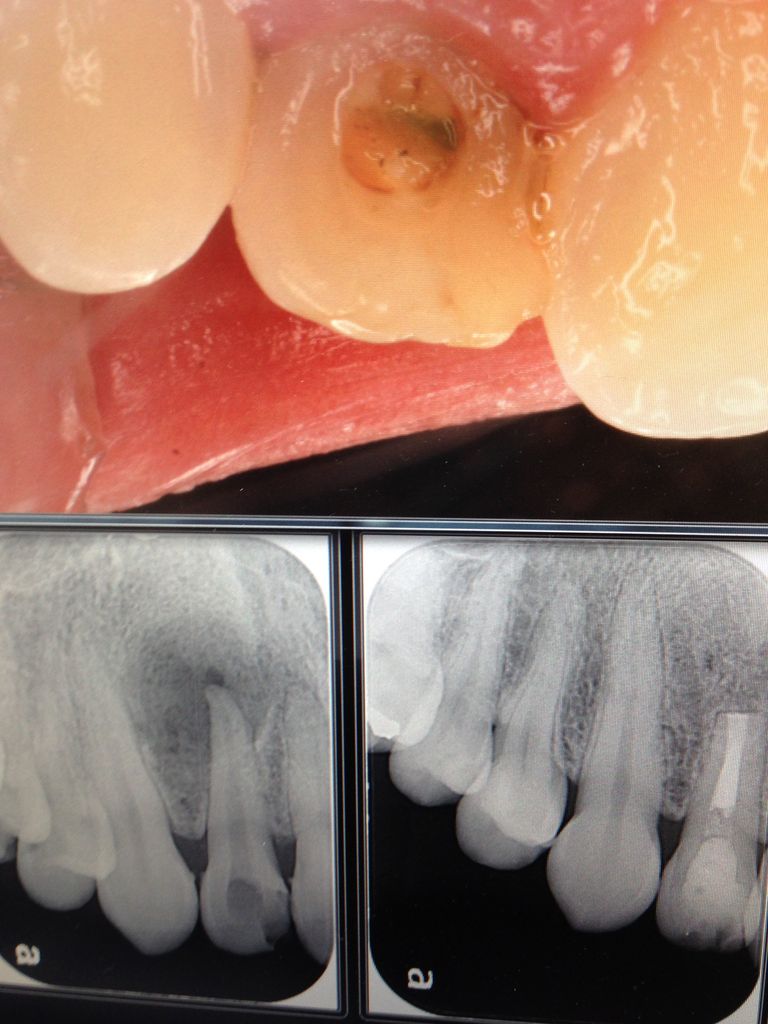

キレイにしたはずの神経から、古い薬のカスが出てきたり

腫れや膿が止まらなかったすれば、最終的な薬を詰めるのに数回かかった方もあります。

せいぜいかかっても、3〜4回だと思います。